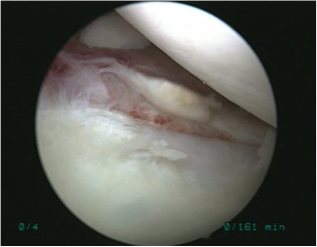

手術所見

| 遊離体 | 遊離体摘出時 |

| 前方関節唇損傷 | 損傷部位を縫合中 | 縫合終了 |